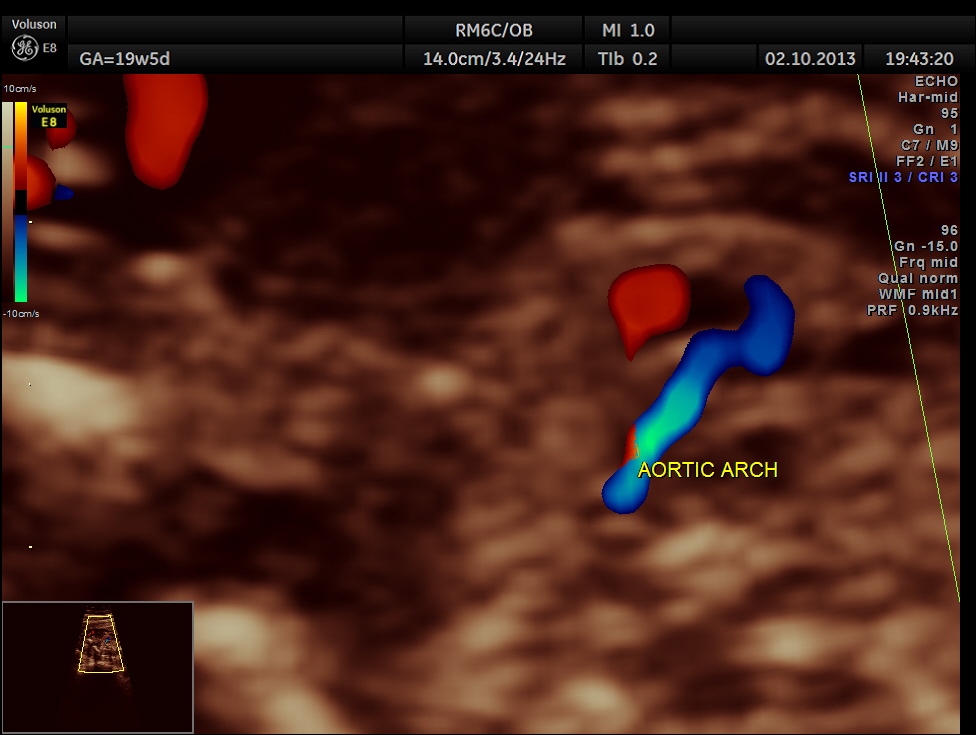

Aortic arch is progressively narrowed with the isthmus appearing very narrow. A flow reversal is also seen .